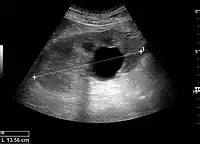

Figure 1. Normal adult kidney. Measurement of kidney length on the US image is illustrated by ‘+’ and a dashed line. *Column of Bertin; ** pyramid; *** cortex; **** sinus.[1]

The kidney is divided into parenchyma and renal sinus. The renal sinus is hyperechoic and is composed of calyces, the renal pelvis, fat and the major intrarenal vessels. In the normal kidney, the urinary collecting system in the renal sinus is not visible, but it creates a heteroechoic appearance with the interposed fat and vessels. The parenchyma is more hypoechoic and homogenous and is divided into the outermost cortex and the innermost and slightly less echogenic medullary pyramids. Between the pyramids are the cortical infoldings, called columns of Bertin (Figure 1). In the pediatric patient, it is easier to differentiate the hypoechoic medullar pyramids from the more echogenic peripheral zone of the cortex in the parenchyma rim, as well as the columns of Bertin (Figure 2).[1]

The length of the adult kidney is normally 10–12 cm, and the right kidney is often slightly longer than the left kidney. The adult kidney size is variable due to the correlation with body height and age; however, normograms for pediatric kidney size are available.[1]

Cortical thickness should be estimated from the base of the pyramid and is generally 7–10 mm. If the pyramids are difficult to differentiate, the parenchymal thickness can be measured instead and should be 15–20 mm (Figure 3). The echogenicity of the cortex decreases with age and is less echogenic than or equal to the liver and spleen at the same depth in individuals older than six months. In neonates and children up to six months of age, the cortex is more echogenic than the liver and spleen when compared at the same depth.[1]